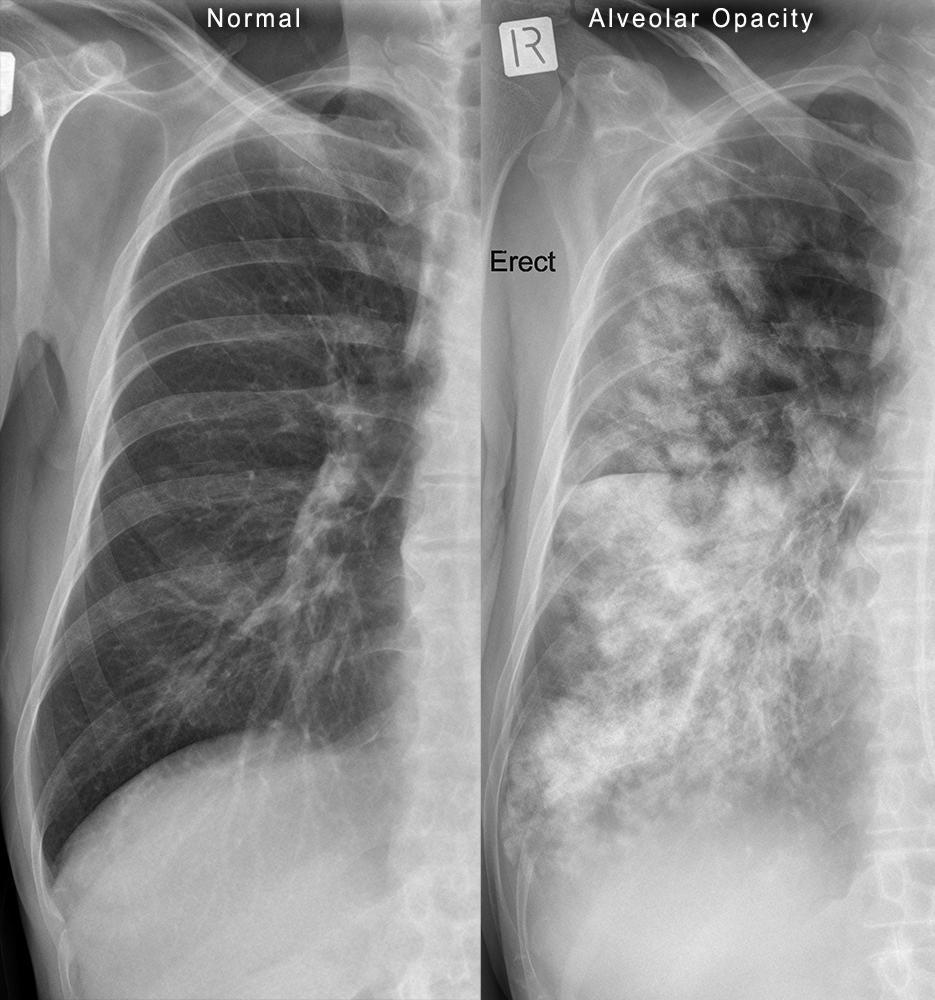

Alveolar filling or collapse intially presents as _____, ill-difined areas of soft tissue opacity. As filling or collapse progresses, these areas spread and coalesce until all air is displaced from the ____ ____.

fluffy- Opacity is often described as fluffy, cotton wool-like, or cloud-like

lung lobe

Interstitial and alveolar patterns differ only in degree of _____. Alveolar pattern is the ONLY lung pattern that can produce ____ _____ opacity in lungs and COMPLETLY obscure pulmonary soft tissue structures.

opacity

soft tissue